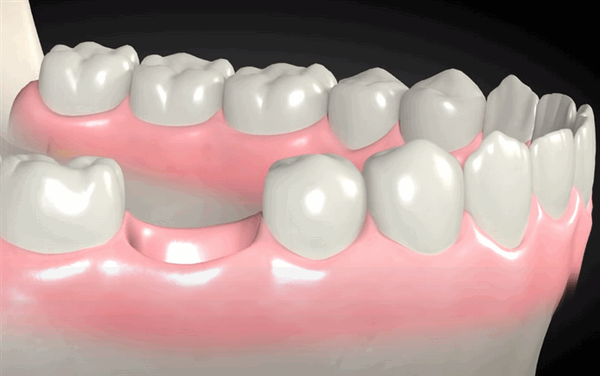

Подготовка зуба к протезированию коронкой

Подготовка к установке коронки после консультации со стоматологом и обследования включает следующие этапы:

- Лечение зуба. На этом этапе проводится лечение кариеса, пульпита, периодонтита. Врач рассверливает зубную единицу, удаляет пораженные ткани, если необходимо, проводит депульпацию, обрабатывает и пломбирует зубные каналы.

- Подготовка коронковой части. Культя зуба восстанавливается пломбой, штифтом, культевой вкладкой. Если проводилось лечение корневых каналов, то пломбу ставят через несколько дней.

- Обточка и снятие оттисков. Зубная единица обтачивается, снимаются слепки с обеих челюстей для правильного соприкосновения единиц после крепления коронки.

- Установка коронки. Обычно ее устанавливают через неделю после снятия оттисков.